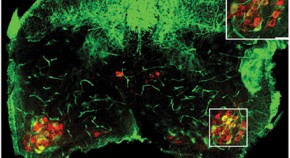

• A new study provides mechanistic insights into how live attenuated simian immunodeficiency virus (SIV) vaccines (LAVs) can protect monkeys from infection with pathogenic SIV. The authors show that replicating LAVs stimulate a protective immune response from a safe haven in the germinal centers of lymph nodes (pages 1673–1681).